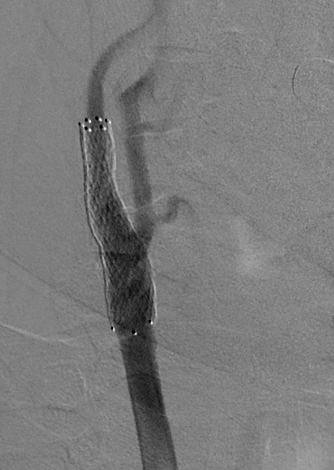

Пациентке в два этапа выполнили стентирование внутренних сонных артерий с обеих сторон. Это привело к значительному улучшению её самочувствия: женщину вскоре выписали домой

Случай 2

62-летний пациент жаловался на частые головные боли, головокружение и появление «мушек» перед глазами. Врачи провели ряд обследований и выявили критическое сужение (на 90%) правой внутренней сонной артерии. Было принято решение в кратчайшие сроки провести операции по установке стента для восстановления нормального кровотока.

После успешного лечения и контрольного обследования не было выявлено никаких нарушений кровообращения. Пациента выписали в удовлетворительном состоянии.

Третьим этапом (22.10.2024) было выполнено стентирование правой внутренней сонной артерии. При контрольном ДС зона реконструкции была проходима.